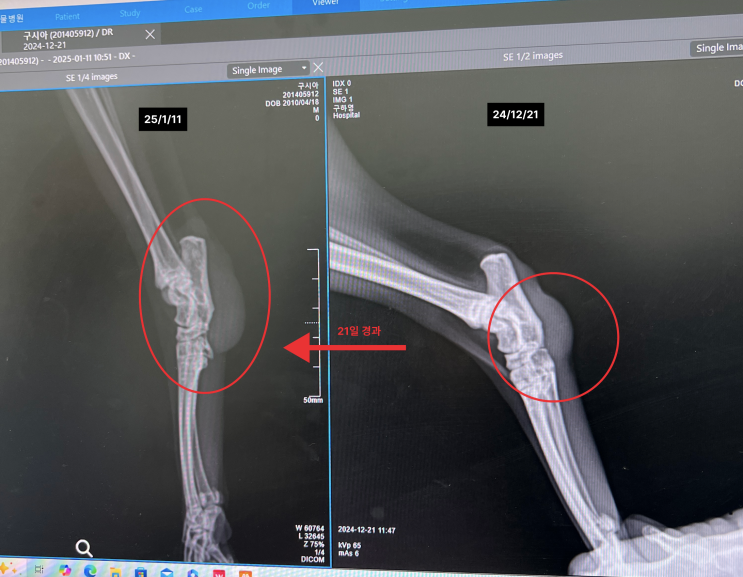

(고양이 연조직육종 재발) 시아 2차 암수술

오늘 울집 고양이 2차 암 수술을 진행했다. 1차 수술한지 97일 만이다. 지금 반차쓰고 수술 끝나길 기다리...